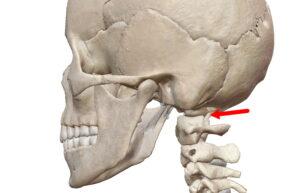

楕円関節

| 球関節の楕円バージョン。楕円なので回旋は出来ない2軸の関節。環椎後頭関節、橈骨手根関節、中手指節関節(母指以外)。 |